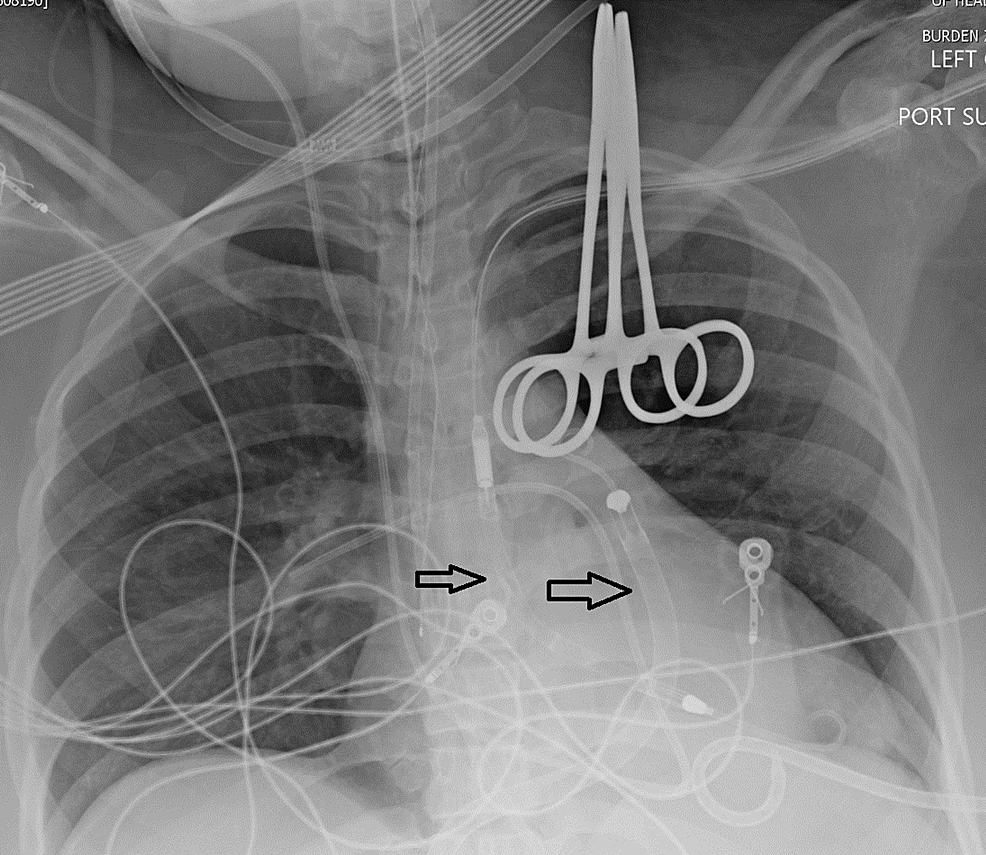

Chest Xray at presentation. The anteroposterior chest Xray showed a Can A Chest X-Ray Show Myocarditis Will often be normal in myocarditis, but it may show features consistent with heart failure. chest radiography is considered usually appropriate in the setting of chest pain in patients with low to intermediate probability. a typical appearance of myocarditis on mri in the correct clinical setting may obviate biopsy. myocarditis is usually suspected based on the patient's. Can A Chest X-Ray Show Myocarditis.

From www.researchgate.net